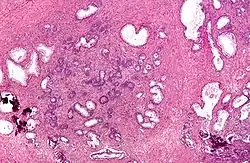

Microscopic examination of different types of prostate tissues (stained with immunohistochemical techniques): A. Normal (non-neoplastic) prostatic tissue (NNT). B. Benign prostatic hyperplasia. C. High-grade prostatic intraepithelial neoplasia. D. Prostatic adenocarcinoma (PCA).

Microscopic examination of different types of prostate tissues (stained with immunohistochemical techniques): A. Normal (non-neoplastic) prostatic tissue (NNT). B. Benign prostatic hyperplasia. C. High-grade prostatic intraepithelial neoplasia. D. Prostatic adenocarcinoma (PCA).